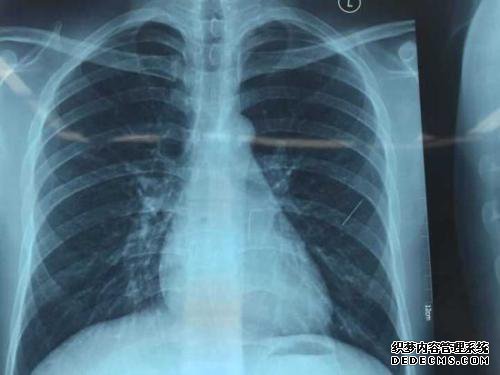

左心室扩张情况如何?非常严重吗?

心脏负荷过大(1)压力负荷过大:也称为过度负荷,是心脏收缩的阻力负荷增加。

在高血压和主动脉流出狭窄(主动脉狭窄,主动脉收缩)中观察到过度的左心室压力超负荷。

(2)过多的电容性负荷:也称为过度的预负荷,当心脏处于舒张期时会过载。

观察到主动脉瓣左室容积超负荷,二尖瓣关闭不全,右或左先天性心脏病或左右分流。

解释:长期过大的压力或过度的容量超负荷会导致左心室向心肥大(心室壁增加而无明显的心室扩大),从而改善并补偿了收缩力,但心脏如果阻力受到限制,如果长期长度过长,心脏将超过其补偿能力,将出现偏心肥大,并且左心室会增加。

2)

原发性心肌病,例如心脏病,扩张型心肌病,继发性心肌病,例如糖尿病,甲状腺疾病,结缔组织疾病,心脏毒性药物和全身浸润性疾病(例如心肌淀粉样变性病)和其他心肌病,酒精性心肌病和围产期心肌病也可引起左心室肥大。